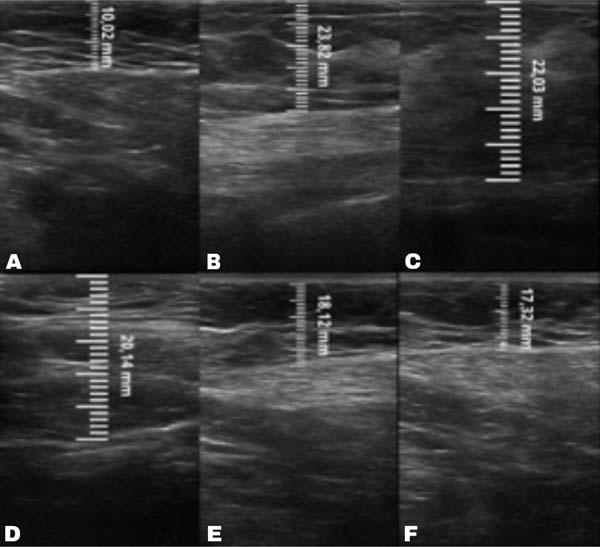

No grupo enxerto decantado, a reducãomédia, comparando-se a espessura inicial apos lipoenxertia, foi de 9,90% no 15° dia, 19,27% no 1° mes, 23,59% no 3° mes e 26,36% no 6° mes. No grupo enxerto filtrado, a reducao media, comparando-se a espessura inicial apos lipoenxertia, foi de 7,74% no 15° dia, 14,85% no 1° mes, 20,67% no 3° mes e 22,80% no 6° mes. ►Fig. 6. A evolução ao ultrassom da espessura do tecido subcutâneo antes e depois da lipoenxertia pode ser vista nas ►Figs. 7-8. Os resultados de pré-e pós-operatório de uma paciente de cada um dos grupos estão exibidos nas ►Figs. 9-10.

Fig. 7 - Ultrassonografia grupo gordura decantada: (A) Pre-operatorio: 10,02 mm. (B) Pós-operatOrio imediato: 23,82 mm. (C) 15 dias depOós-operatório: 22,03mm. (D) 1 mês de pos-operatorio: 20,14mm. (E) 3 meses de pos-operatorio: 18,12mm. (F) 6 meses de pos-operatorio: 17,32mm.